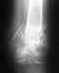

Добрый день.7 месяцев назад был перелом внутренней лодыжки с разрывом д м/б синдесмоза.1,5 месяца назад удалили болт-стяжку и сейчас в результате оказалось что расстояние от вилки до таранной кости на 3 милиметра превышает то, что должно быть (в сравнении с другой ногой).

Как я понимаю расхождение синдесмоза произошло из-за недожатого винта. Т.к. развития артроза хочется избежать предполагается оперативное вмешательство с удаление рубцов и новым заживлением связок.Насколько вероятно то, что синдесмоз разошелся от недожатого винта?Что стоит сейчас делать?